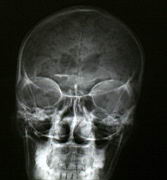

Air in the skull from a stabbing -- "pneumocranium" |

CT of same patient |

| My one-month radiology rotation was an absolute pleasure, as the residents and staff welcomed me warmly right from the start. Doing an elective abroad as a senior resident, one year away from writing the final exams, is in my opinion a much better choice than traveling as a medical student. One knows a lot more and can actually contribute (I dictated numerous X-rays, especially in the pediatric hospital, and did a CT arthrogram of the shoulder since that afternoon I was the person in the department with the most experience). Seeing a different patient group and pathology at this stage is a great way to "shake up" one's medical knowledge -- for example I now have a much better sense of when to include TB in the differential diagnosis, and also of how important it is to think of TB or HIV. Even trauma is different in South Africa -- the people here have figured out that stabbing someone in the eye is very effective at crippling them, and while I have never seen this done in Edmonton I saw two in the same morning in Cape Town!